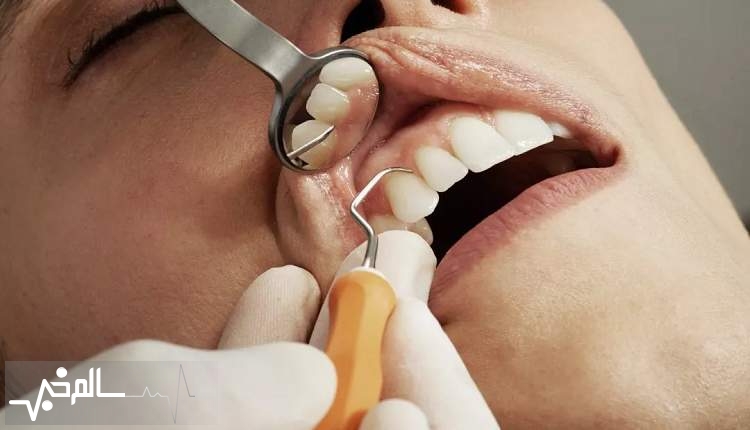

۵۰ درصد از ایرانی ها دچار بیماریهای دهان و دندان هستند

سالمخبر: معاون بهداشت وزارت بهداشت و درمان، گفت: نیمی از جمعیت کشور از عوارض ناشی از بیماریهای دهان و دندان رنج میبرند.

حسین فرشیدی، در همایش پویش ملی سلامت دهان و دندان، گفت: بسیاری از بیماریها از جمله فراموشی و سرطان بر اثر عدم رعایت بهداشت دهان و دندان است.

وی افزود: باید به سبک زندگی سالم برای پیشگیری از ابتلاء به بیماریهای غیر واگیر در زمینه بیماریهای دهان و دندان توجه شود.

معاون بهداشت وزارت بهداشت گفت: نباید فقط به شناسایی بیماریهای غیر واگیر و درمان آن اکتفا کرد بلکه باید از ابتلای دیگر هموطنان به این بیماریها از جمله بیماریهای دهان و دندان پیشگیری کرد.

فرشیدی افزود: باید همانند غربالگری فشار خون و دیابت که پارسال در کشور انجام شد بیماریهای دهان و دندان نیز در شبکه نظام سلامت غربالگری شود تا توجه مردم به این بیماری و روشهای پیشگیری از آن جلب شود.

وی گفت: هزینه درمان بیماریهای دهان و دندان بالاست زیرا در طول سالها این بیماریها ایجاد شده و درمان نشده باقی مانده است، از این رو باید به خود مراقبتی و توجه به سلامت دهان و دندان در برنامه سلامت خانواده توجه شود.

معاون بهداشت وزارت بهداشت ادامه داد: وزارت بهداشت در تأمین تجهیزات و پشتیبانی از ارتقای سلامت خانواده و افزایش سلامت دهان و دندان با هدف پیشگیری از ابتلاء به این نوع بیماریها آماده همکاری است.

فرشیدی افزود: استفاده از هوش مصنوعی به ویژه برای تشخیص عکسهای پزشکی در ارتقای سلامت دهان و دندان کشور مفید خواهد بود.